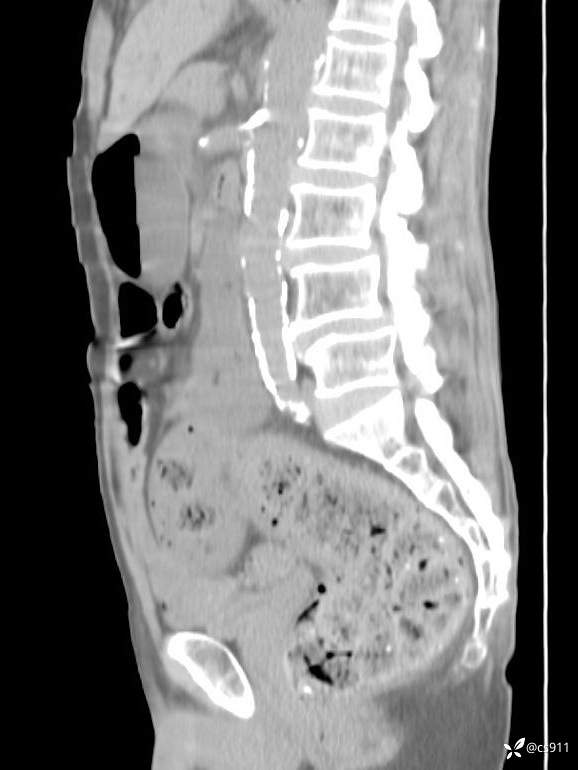

急腹症之急诊CT,原因?答案公布

男,77岁,腹痛、腹胀伴恶心呕吐1天。呕吐胃内容物,非喷射性呕吐,有咖啡色样胃内容物,诉有胃穿孔病史。查体:全腹平,下腹部压痛,全腹无反跳痛,叩诊呈浊音,移动性浊音阴性,肠鸣音减弱,1-2次/分。肛检:直肠未扪及明显肿物,可触及大量粪块。

T 36.6℃ P 80次/分 R 26次/分 BP 100/60mmHg

白细胞(WBC) H 14.55 10e9/L 4-10

中性粒细胞百分率(NEUT%) H 85.7 % 40-75

血淀粉酶(AMY) HH 1859 U/L 35-135

癌胚抗原(CEA) H 27.44 ng/ml 0-5

呕吐物 潜血试验 * 阳性 阴性

患者轮椅入室检查神志清楚, 能配合摆位和呼吸